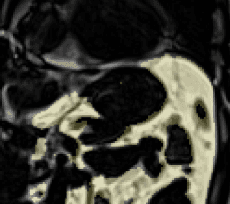

AI-based annotation of your body

Easily understand highly technical scans.

Your recent health check-up provides a detailed overview of your health, showing some very positive developments alongside a few areas that warrant attention. The most notable findings are related to age-appropriate wear-and-tear in your spine. The MRI shows disc bulges in your neck and lower back, with one in your lower back causing a moderate narrowing of the spinal canal, which can sometimes affect nerves. Your blood tests indicate a persistent elevation in a type of white blood cell called eosinophils, which can be a sign of an allergic or inflammatory process, and may be linked to fluid seen in the air cells behind your ears. We also noted a mild reduction in your kidney filtration rate, which often varies and can be influenced by factors like hydration. On a very positive note, your results show excellent improvements in your metabolic health. Your blood sugar and cholesterol values are now in an ideal range, which is a wonderful achievement and greatly benefits your cardiovascular health. Furthermore, your body composition is outstanding, with very low levels of abdominal and liver fat. Other findings, such as small, simple cysts in your liver, are common and not a cause for concern. You will find more details on all these points in the full report below.